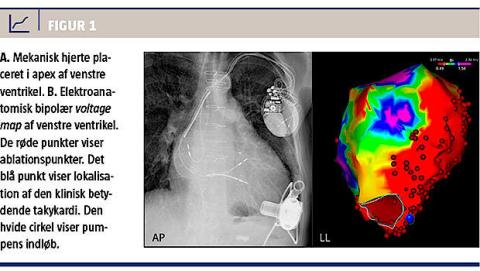

En LVAD af typen Heartware blev implanteret i apex af venstre ventrikel med udløb til aorta descendens (Figur 1A). I den første postoperative uge blev enkelte episoder med vedvarende monomorf ventrikulær takykardi kardioverteret. Efter optimeret medicinsk behandling med reduktion af afterload og lungekarmodstand blev patienten stabiliseret og udskrevet efter en måneds indlæggelse. Tre måneder efter implantationen blev han indlagt med febrilia og inkompensatio, men på trods af effektiv behandling heraf konstateredes tiltagende episoder med monomorf ventrikulær takykardi. Selvom der blev påbegyndt maksimal antiarytmisk behandling med amiodaron, lidocain og betablokker, endte patienten i en tilstand med medicinsk refraktær elektrisk storm og langvarig ventrikulær takykardi. Med baggrund i hæmodynamisk dekompensation på grund af højresidig svigt sekundært til ventrikulær takykardi fandt man indikation for subakut radiofrekvensablation.

I generel anæstesi med transvenøs og transseptal adgang identificerede man store områder med fraktionerede og sene signaler ved elektroanatomisk

kortlægning af venstre ventrikel (Figur 1B). Under igangværende takykardi lokaliseredes patientens

dominerende kliniske ventrikulære takykardi til kanylen i LVAD-indløbet. Takykardien termineredes

succesfuldt under ablation. Ved programmeret stimulation kunne man herefter inducere en anden, men ikke klinisk takykardi, der var lokaliseret til den basale del af venstre ventrikel og således med afstand til LVAD-indløbet. Her blev takykardien ligeledes termineret under ablation. Endelig ablaterede man på sene og fraktionerede signaler i arvævsområdet. Ved procedurens afslutning kunne der ikke længere induceres ventrikulær takykardi ved programmeret stimulation fra ventriklen.